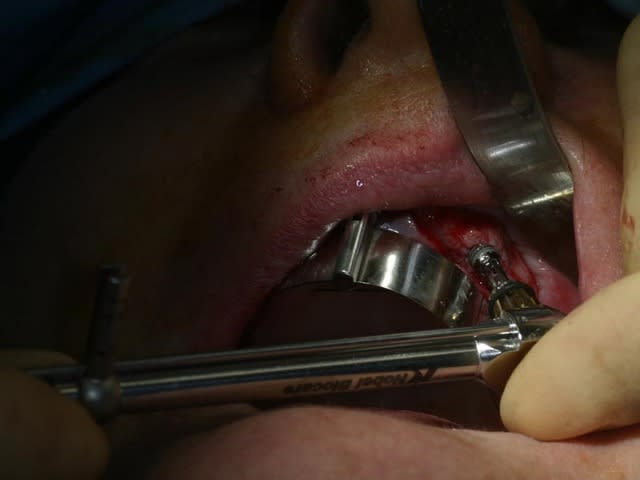

bon, toujours aussi speed je suis, mais après certaines réclamations, et malgrès ma réticence à poser un cas non "consolidé", voici en avant première mon premier all on 4, version photos ratées et non retouchées, mais... speed je suis je vous disais ;)

sto le bla bla, et pasons le diaporama... bon voyage au pays de la mise en charge immédiate totale au maxillaire de fille carole sur dame ginette, une patiente en or que j' adore, et pour qui je suis très très heureuse d' avoir pu réaliser cette chirurgie et la première étape prothétique.....